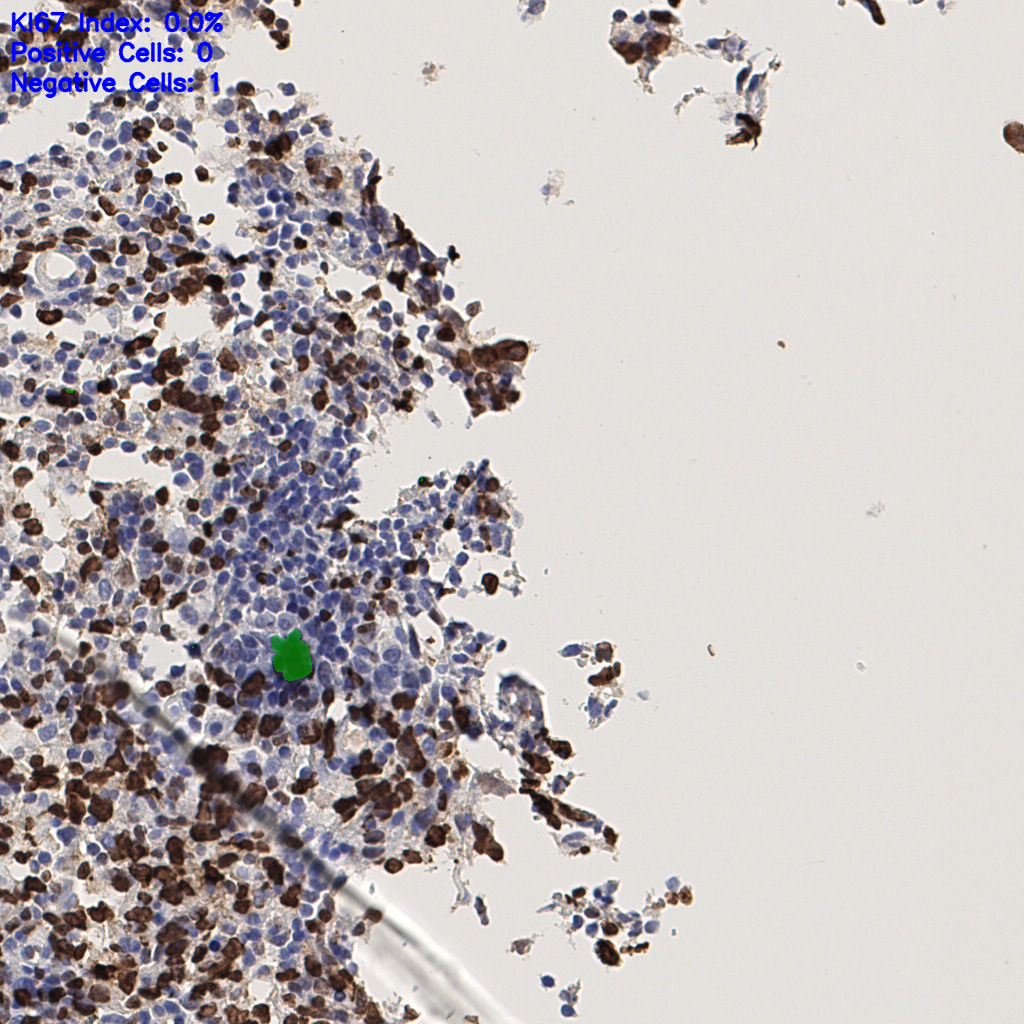

7.85%

Ki67 指数

阴 1104

阳 94

切片统计

总切片

1953

有效

288

已标记

有效率

15%

标记后

标记前